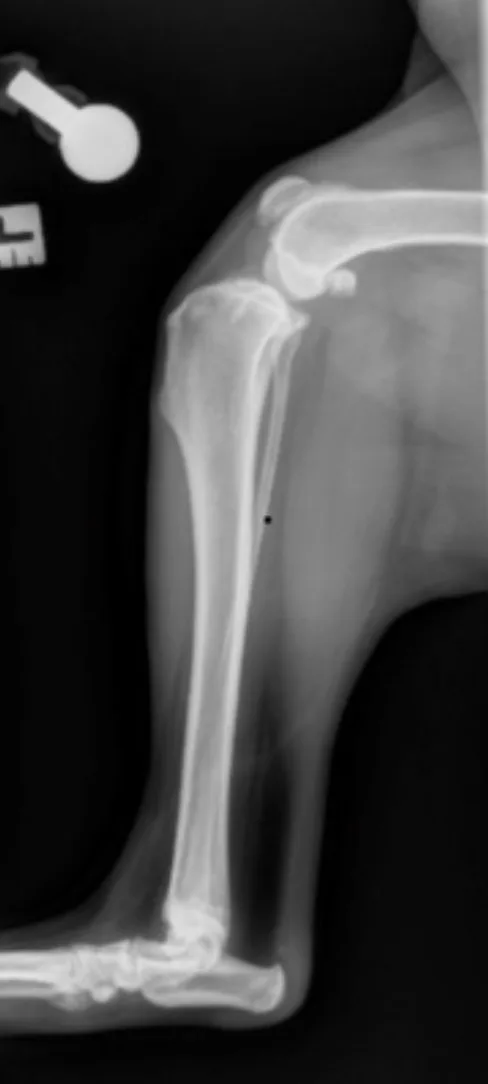

Place the patient in lateral recumbency with the affected limb on the table. Hold the limb or use positioning tools to keep the stifle and hock at a 90-degree angle. If needed, use gauze or a foam pad to elevate the tarsus and ensure the stifle joint does not rotate. Abduct the unaffected limb up and away from the table toward the patient’s back.

This positioning is ideal for planning some stifle surgeries (eg, tibial plateau-leveling osteotomy). For some procedures (eg, tibial tuberosity advancement), extending the stifle to a standing angle (≈135 degrees) is preferred.

Center the collimator beam over the tibia to include both the stifle and tarsal joint.

Author Insight

On the radiograph, the stifle and tarsus should be at an »90-degree angle. The patella should be cranial (white arrow), and the medial and lateral femoral condyles should be as superimposed as possible. The medial and lateral fabellae should have near superimposition to each other (black arrow).